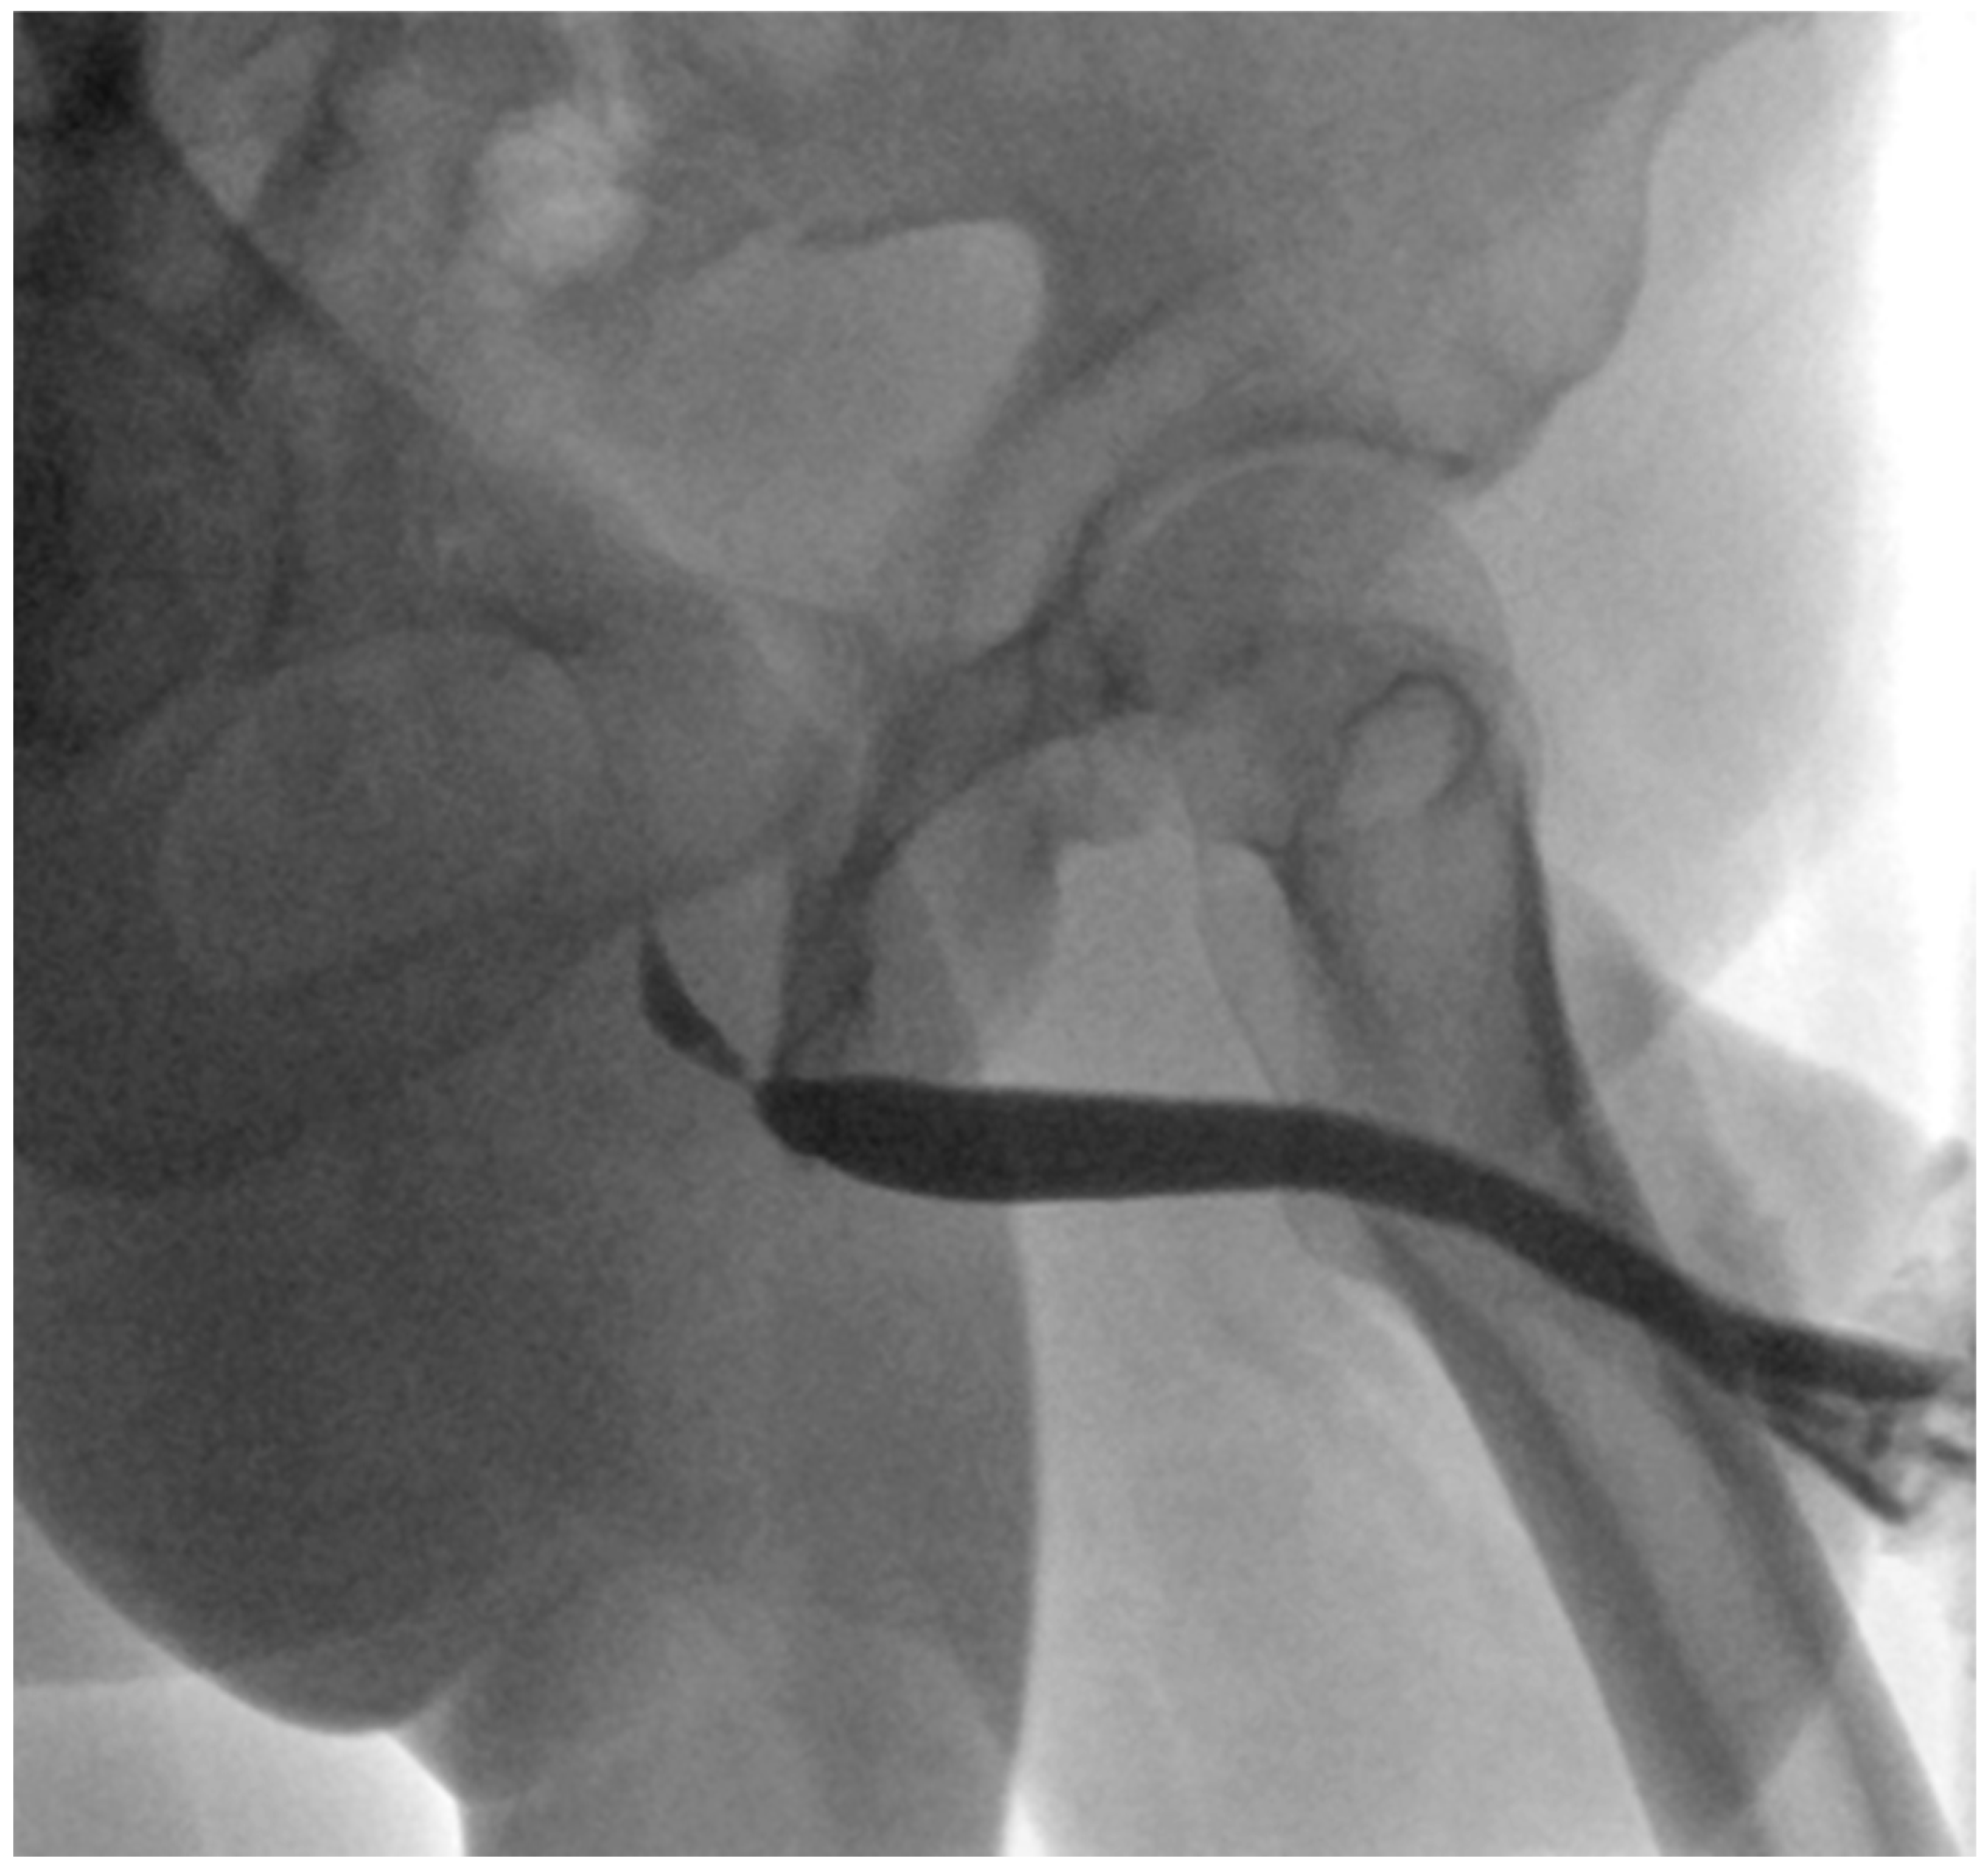

4. Case Report